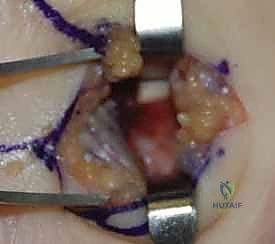

2. التدخل الجراحي الدقيق (باستخدام المنظار أو الفتح المحدود)

بدلاً من الشقوق الكبيرة التقليدية، يُفضل الدكتور هطيف استخدام شقوق صغيرة جداً بمساعدة منظار المفصل (Arthroscopy) أو الجراحة الميكروسكوبية، مما يقلل من تلف الأنسجة المحيطة ويسرع الشفاء.

3. إرجاع العظم إلى وضعه التشريحي (Reduction)

تحت توجيه الأشعة السينية المباشرة داخل غرفة العمليات (C-arm)، يتم إرجاع قطع العظم المكسورة إلى مكانها الطبيعي بدقة متناهية لا تقبل الخطأ حتى بمليمتر واحد، لأن أي اعوجاج سيؤدي إلى خشونة مبكرة في المفصل.

4. التثبيت الداخلي (Internal Fixation)

يتم تثبيت العظام باستخدام أدوات طبية متناهية الصغر مصنوعة من التيتانيوم.

* أسلاك كيرشنر (K-wires): تُستخدم للتثبيت المؤقت أو في الكسور البسيطة.

* المسامير بدون رأس (Headless Compression Screws): تُدفن بالكامل داخل العظم لتجنب احتكاكها بالأوتار، وتوفر ضغطاً ممتازاً لسرعة التئام الكسر.